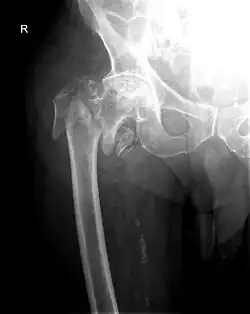

Pertrochantäre Femurfraktur

Pertrochantäre Femurfraktur oder Oberschenkelfraktur ist der medizinische Fachbegriff für einen hüftgelenknahen Knochenbruch des Oberschenkelknochens (Femur) im Bereich zwischen großem und kleinem Rollhügel (Trochanter major und Trochanter minor) und ist eine der häufigsten Knochenbrüche vor allem älterer Menschen mit einem hohen Mortalitäts- und Morbiditätsrisiko.

Röntgenaufnahmen des Hüftgelenkes in zwei Ebenen bestätigen die Diagnose. Bei strittigen Fällen kann eine Computertomographie (CT) durchgeführt werden.